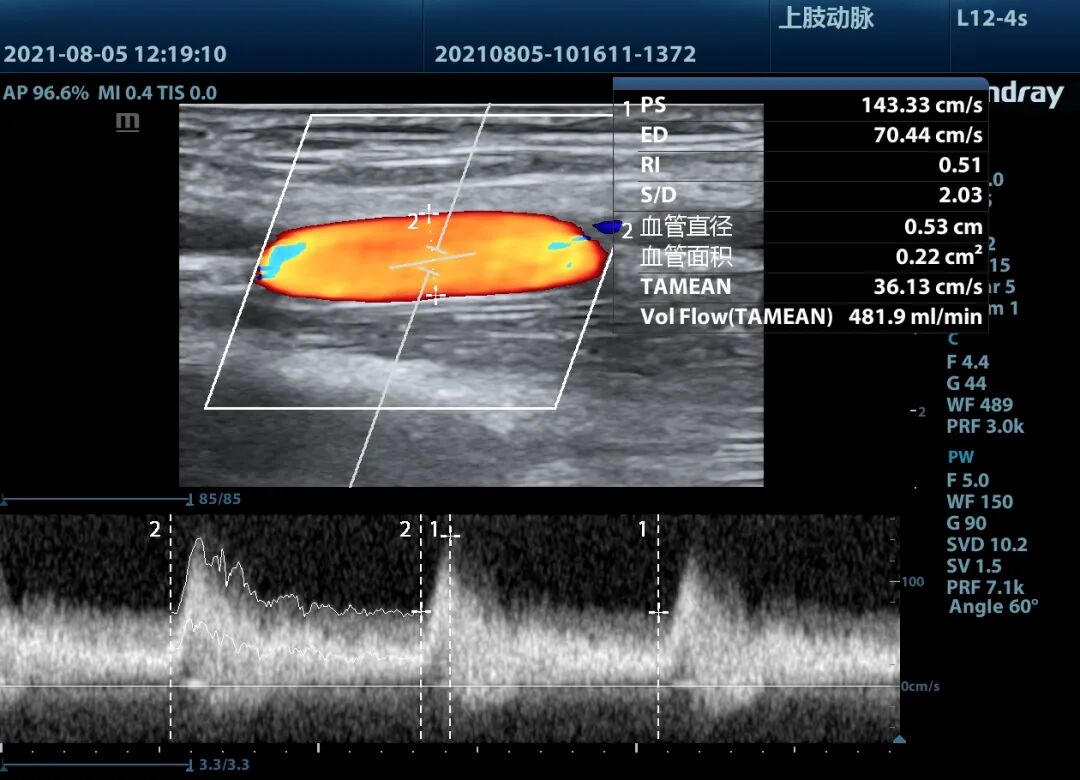

▲球囊继续加压,血管狭窄部出现双凹征逐渐消失

超声实时观察球囊扩张状态,直至球囊压迹消失,最后超声显示狭窄段血管完全再通,手术取得成功。

▲术后头静脉血流量满足血液透析要求